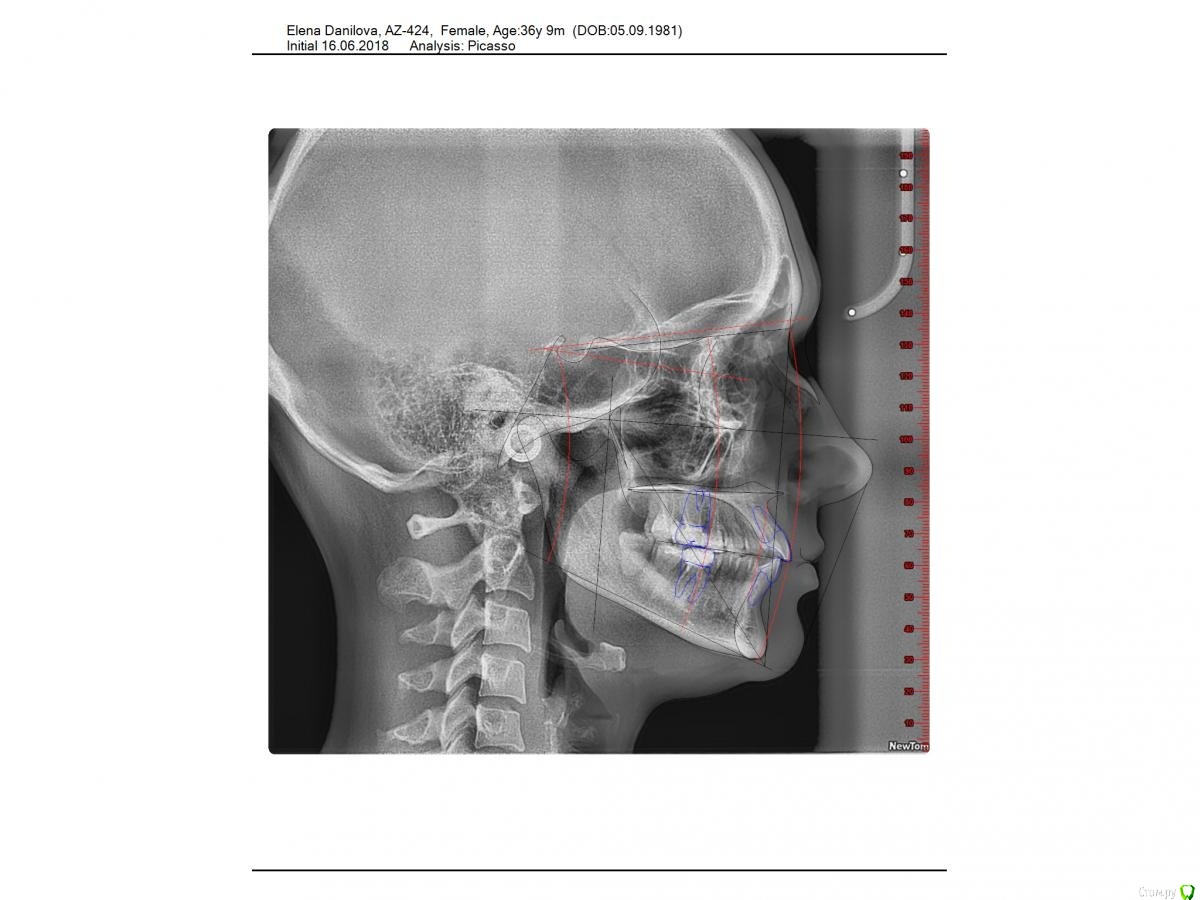

Dkat Опубликовано 10 ноября, 2020 Поделиться Опубликовано 10 ноября, 2020 Добрый день! Подскажите, возможно ли в моем случае лечение только брекет системой или нужна хирургическая коррекция положения челюстей? Ссылка на комментарий

Дмитрий Л. Опубликовано 10 ноября, 2020 Поделиться Опубликовано 10 ноября, 2020 Возможно. Хирургия не нужна. Это не скелетный. И не третий. 1 Ссылка на комментарий

Dkat Опубликовано 12 ноября, 2020 Автор Поделиться Опубликовано 12 ноября, 2020 Спасибо! Очень неожиданно - на основе обследований мне ставят 3 скелетный класс. Попробую проконсультироваться у других ортодонтов.Данилова Е.И. Заключение (1).pdf Ссылка на комментарий